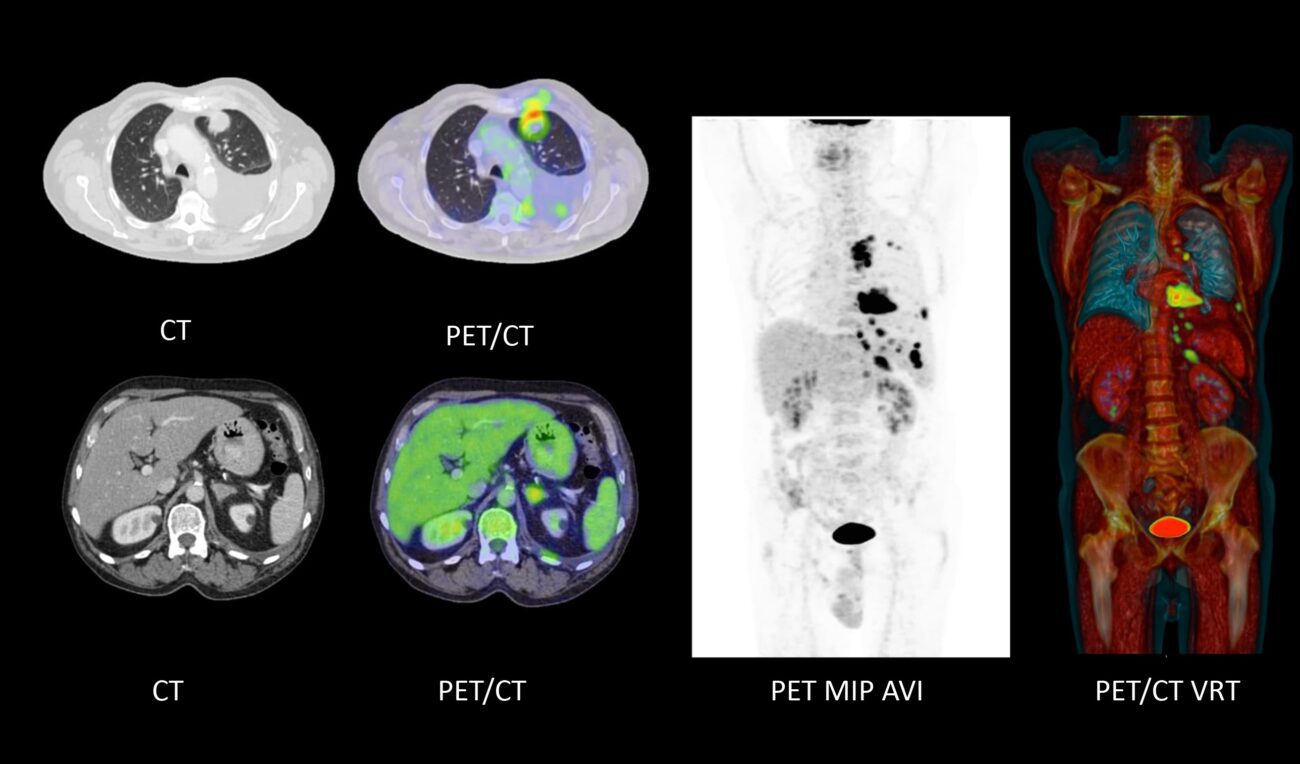

Nos complace anunciar la incorporación del PET-CT/Scan con el avanzado Biograph™ mCT de Siemens, una tecnología de vanguardia que optimiza la detección y seguimiento del cáncer.

El PET CT/Scan (Tomografía por Emisión de Positrones) es un procedimiento no invasivo que identifica cambios metabólicos en el cuerpo, ideal para diagnosticar, monitorear y prevenir la progresión del cáncer.

Es un equipo especializado que combina lo mejor de las tecnologías PET (Tomografía por Emisión de Positrones) y TC (Tomografía Computarizada). Este dispositivo avanzado tiene un túnel grande y un diseño pensado para facilitar tanto el trabajo de los especialistas como la experiencia de nuestros pacientes.